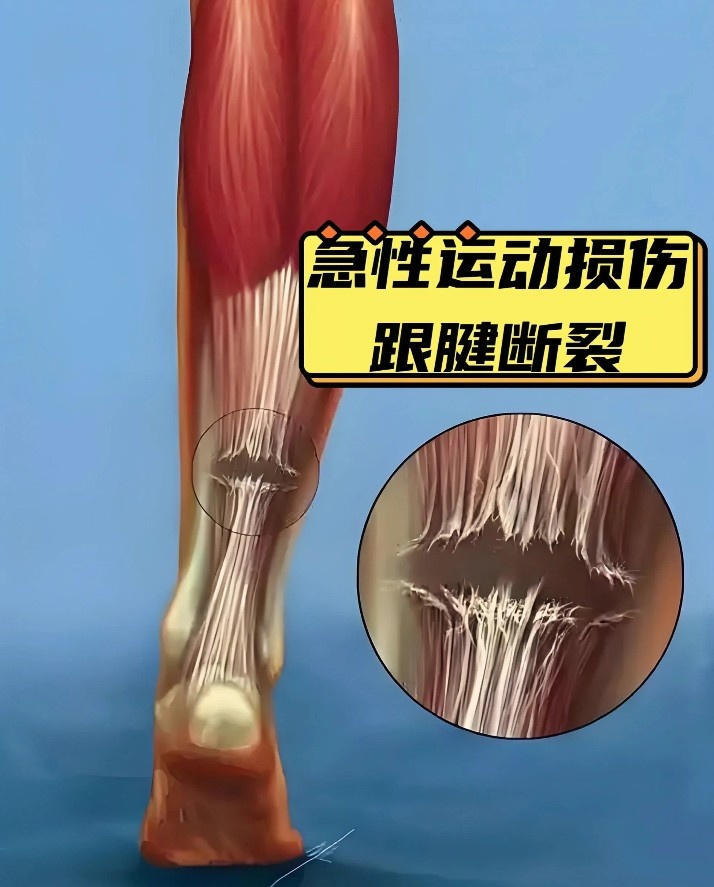

一、 什么是跟腱撕裂?

跟腱是人体最粗壮、最强大的腱性组织,连接着小腿后方的腓肠肌、比目鱼肌与跟骨。它是球员完成起跳、冲刺、急停等爆发性动作的动力核心。

损伤机制: 绝大多数跟腱撕裂发生在爆发性发力瞬间。当足部过度背伸(如准备蹬地起跳)或强力跖屈(如加速推进)时,巨大的应力超过了腱纤维的承受极限,导致其像紧绷的琴弦一样断裂。

为何是“无对抗”? 这正是长期微损伤累积的结果。跟腱内的血液供应相对贫乏,一旦长期处于高负荷下,微小的退行性改变(即老化或磨损)无法及时修复,最终在一个寻常的蹬地动作中发生突发性断裂。

而从解剖结构上看,跟腱在距离脚后跟(跟骨结节)上方约3到6厘米处是最窄的,而且这个区域的血液供应非常差。这意味着该部位在日常训练中产生的微小损伤很难得到充足的营养来快速修复,因此这里也成为了跟腱最容易发生断裂的“危险区”。